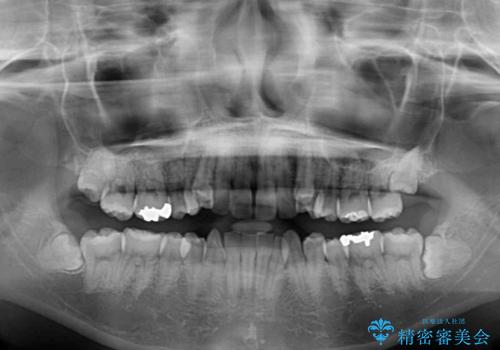

- 下の前歯のデコボコを気にして来院された患者様です。

来院当初、上顎の八重歯は気にしていらっしゃらなかったのですが、矯正治療をするのであれば、しっかりと治した方が良いと説明し、全顎矯正を行うこととしました。

八重歯の移動量が多く、インビザライン単体での治療は困難と判断し、補助装置により八重歯移動後にインビザラインを用いることとしました。